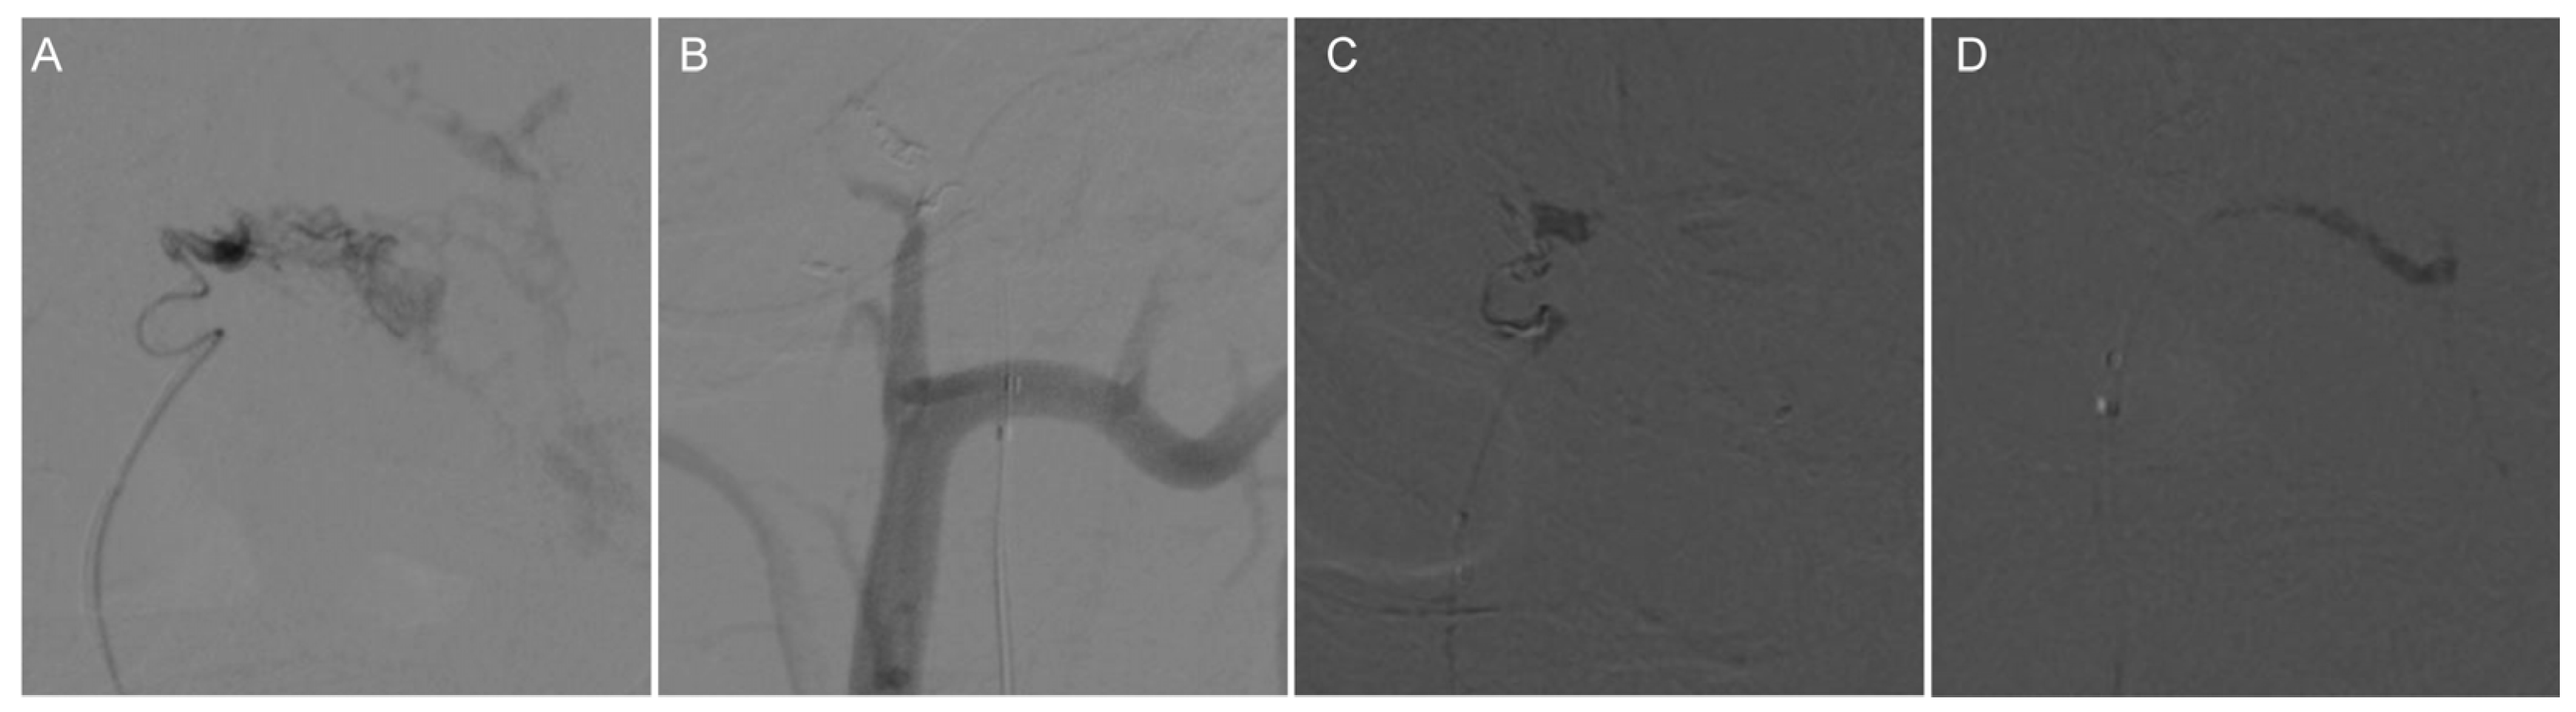

Figure 2.

Preoperative DSA of the AVF showed that the right ascending pharyngeal artery served as the donor artery, and the spinal veins and occipital cortex veins served as the draining veins. (A) Preoperative imaging (frontal view); (B) Preoperative imaging (right-sided view); (C) Preoperative imaging (left-sided view).